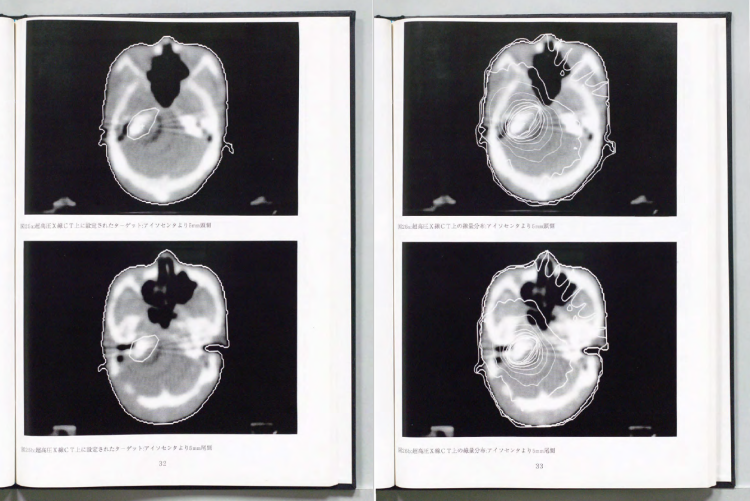

中川:今の大学院生はローカルな話題で学位をとるけど、当時は学位論文といえばもっと壮大な研究をやっていました。私の研究も、機器開発+医学物理+臨床とでもいいましょうか。当時は医学物理士なんて日本にいないですからね。全部自分でやらなくてはいけなかった代わりに、壮大なことができた時代でもありました。

(説明しながら学位論文をみせる)

中川:まずタングステン酸カドミウムクリスタルからフォトダイオードを作って、それを256個並べて 検出器を作るんですね。それで治療器の上でCTをとれる機械を開発しました。マルチリーフコリメーターも開発して。同室CTといって、診断CTと治療CTを同じ部屋に置くわけです。だから今では当たり前にやっているIGRTの技術だけど、私が学位論文でやったのが最初だったというわけです。1990年頃 、正確には学位論文になったのは1989年ですから、そのころの話です。その日のうちに帰ったことなんてなかったですよ。